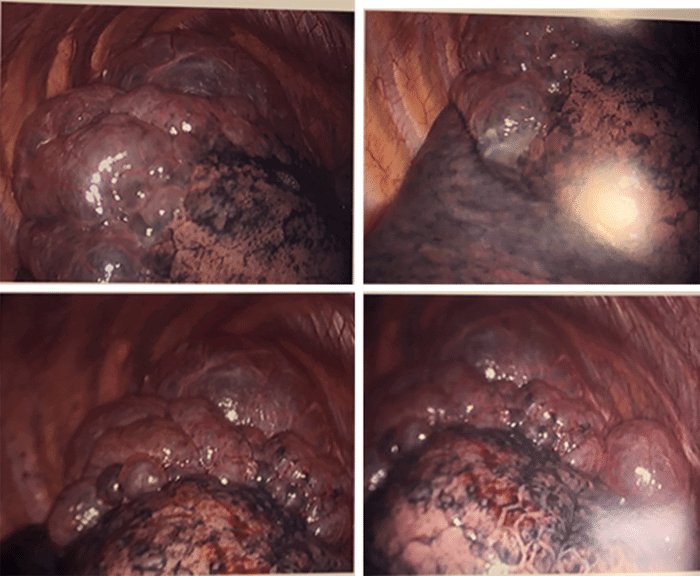

After discussing the high likelihood for recurrence with the patient, the decision was made to proceed with bullae resection and pleurodesis. The patient underwent uncomplicated video-assisted thoracoscopy with right-upper lobe wedge resection of the bullae and mechanical pleurodesis (Figure 3). His postoperative course was as expected, and his chest tube was removed on postoperative day three before his discharge home.

Figure 3. Intraoperative Finding of Large and Small Bullae of Right Upper Lobe. Published with Permission